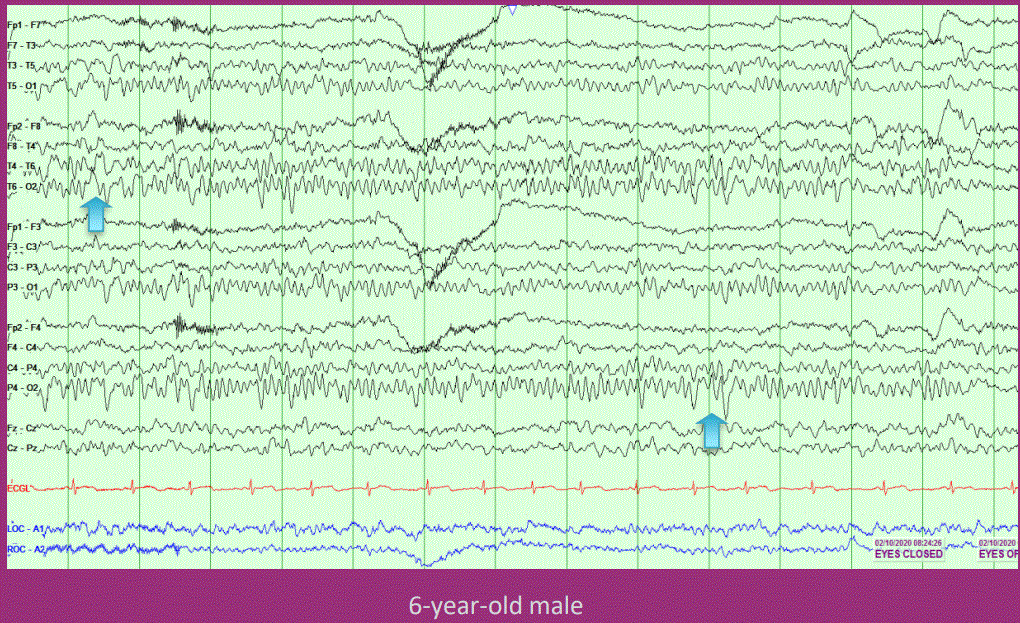

Posterior slow waves of youth

Typically seen ages 6 to 12